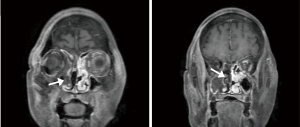

After admission, laboratory tests indicated random blood glucose (GLU) level of 12.74 mmol/L (normal value ≤11.1 mmol/L), base excess (BE) level of −3.4 mmol/L (normal range, −3 to +3 mmol/L), β-hydroxybutyric acid (β-Hb) level of 3.61 mmol/L (normal range, 0.02–0.27 mmol/L), white blood cell count (WBC) level of 17.44×109/L (normal range, 3.69–9.16/L), procalcitonin (PCT) level of 0.46 ng/mL (normal range, 0.00–0.05 ng/mL) and interleukin-6 (IL-6) level of 317 pg/mL (normal range, 0.00–7.00 ng/mL). Considering the presence of infection and diabetic ketoacidosis, the patient was given symptomatic treatment such as hypoglycemic therapy, ketone body lowering measures, and empirical anti-infection. A head computed tomography (CT) scan revealed a cerebral infarction in the right parietal lobe (Figure 1A). On hospital day 7 (2023-09-02), the patient’s mental status deteriorated to shallow coma. Follow-up cranial CT demonstrated progression of the cerebral infarction with concomitant cerebral herniation (Figure 1B). Cerebrospinal fluid (CSF) analysis showed leukocytosis (326×106/L; normal: 0–8 ×106/L) and elevated microalbumin (86.1 mg/dL; normal: 8.0–43.0 mg/dL). Concurrent metagenomic next-generation sequencing (mNGS) of CSF detected Rhizopus oryzae (76 sequences), confirming intracranial mucormycosis. Fungal meningitis (Rhizopus oryzae) complicated by cerebral infarction was diagnosed based on clinical and ancillary findings. Emergency right frontotemporal-parietal debridement with dural repair and intracranial pressure transducer placement was performed that day. The patient maintained stable vital signs intraoperatively, and postoperative cranial CT was obtained (Figure 1C). By September 9, 2023, surveillance cranial CT (Figure 1D) showed unchanged right hemispheric infarction extent with normalized density and resolved cerebral edema. On the second day of admission (2023-08-28), contrast-enhanced cranial MRI (Figure 2) demonstrated multiple right hemispheric infarcts. Contrast-enhanced orbital MRI (Figure 3) revealed soft tissue swelling in the right maxillofacial region and bilateral periorbital areas. After enhanced scanning, prominent enhancement was noted, suggesting infectious lesions and multiple groups of sinusitis. At the same time, CSF mNGS confirmed Rhizopus oryzae infection (as above). After identification of the pathogenic bacteria, liposomal amphotericin B (L-AMB) and posaconazole suspension were administered for antifungal treatment. Additionally, serial monitoring of infection markers—including complete blood count, PCT, and IL-6—showed progressive improvement (Figures 4,5).

According to the radiologic extent of the disease, the severity of the disease is categorized into three stages. At Stage I, the disease is only limited to the nose and sinuses. At Stage II, the disease includes the spread to the orbit, hard palate, and mouth which can be surgically resected with the lowest complication rate. At Stage III, the disease is manifested as intracranial involvement. ROCM may extend to the pterygopalatine fossa by direct erosion of the sinus wall or by perivascular or perineural spread. Involvement of the pterygopalatine fossa forms a pathway for infection into the middle cranial fossa and cavernous sinus (7). As a result, some studies have recommended that all patients who are suspected with ROCM should undergo a comprehensive evaluation of the pterygopalatine fossa (8). The absence of enhancement on MRI of the nasal and sinus mucosa which is called the black turbinate (BT) sign represents tissue inactivation and necrosis due to microvascular invasion. The BT sign can be apparently seen in the patient mentioned in this paper (Figure 6).

In this case, the patient’s initial symptom was a periorbital skin infection, which subsequently manifested as symptoms of orbit apex syndrome. With further imaging, it revealed multiple infarct foci in the right cerebral hemisphere. According to the facts that the existence of the patient’s diabetes mellitus and risk factors for cerebral infarction, primary cerebral infarction could not be ruled out. In combination with the patient’s past medical history of facial infections and diabetes mellitus, the patient’s relevant pathogenetic examinations including NGS were performed on the second day of admission. Additionally, the presence of Rhizopus oryzae infection was shown on the return of the mNGS of the CSF sent for examination, which was ultimately considered to be a cerebral infarction secondary to a fungal infection, namely ROCM. Non-enhancing hypointense mucosa (“black turbinate sign”) observed on contrast-enhanced MRI in this case reflects microthrombosis and mucosal necrosis caused by vascular invasion of Mucorales. This imaging feature is highly consistent with histopathological ischemic necrosis and serves as an early warning marker for acute invasive fungal sinusitis (9). Notably, although mucosal thickening may also occur in ordinary sinusitis, its enhancement pattern is typically homogeneous, whereas the focal non-enhancement areas associated with the BT sign represent a key distinguishing feature. Subsequently, antifungal therapy was promptly initiated and surgery was performed to treat the intracranial lesion, achieving good effectiveness.